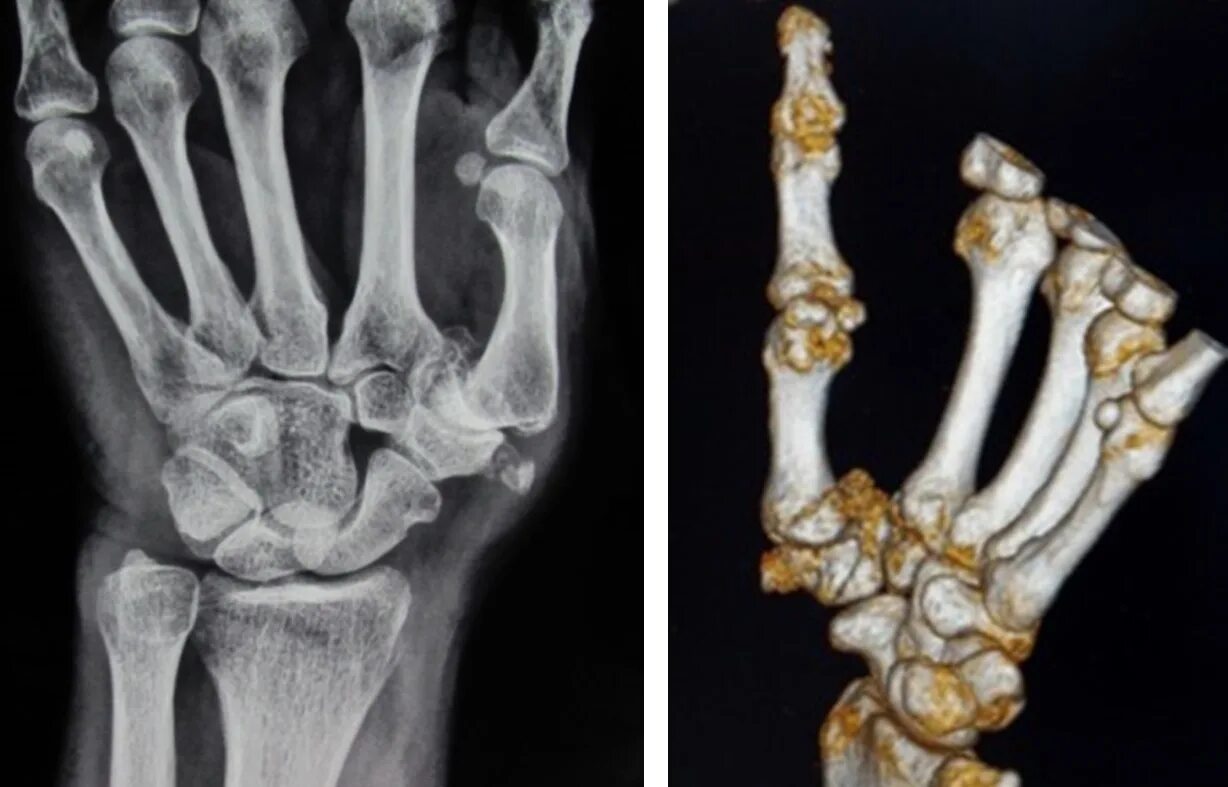

Артроз запястно пястного сустава